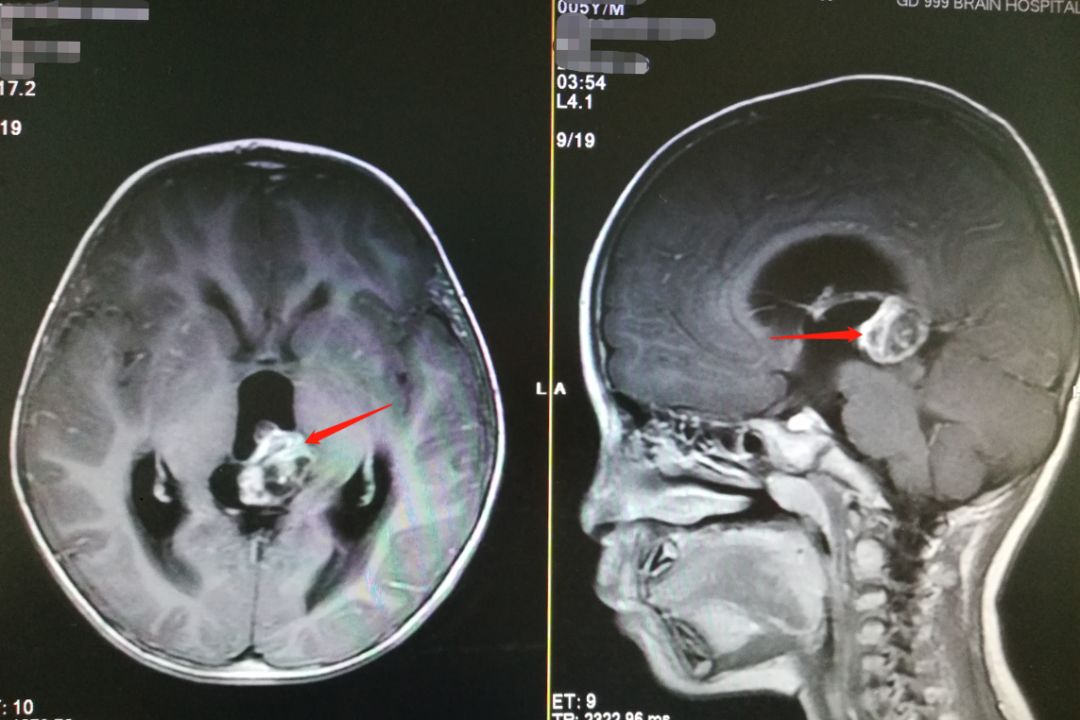

吃了几天感冒药后,小智仍说自己头痛,常常哭闹。刘女士见孩子也没有流鼻涕、咳嗽,她开始担心导致孩子头痛的可能不是感冒,于是又带他到上级医院检查。听说小智已经头痛了将近一个星期,加上期间并无外伤,为明确小智头痛的原因,医生为他做了头颅磁共振检查。检查结果显示小智的松果体区存在占位性病变,医生怀疑是脑肿瘤。

▲患儿术前MR检查

刘女士带着孩子来到广东三九脑科医院时,我院副院长、神经外五科主任鲁明发现患儿的精神状态比较差,他又仔细查看了患儿的影像资料,发现患儿松果体区有高密度阴影,并伴有明显的梗阻性脑积水,认为患儿颅内病变是畸胎瘤的可能性较大。